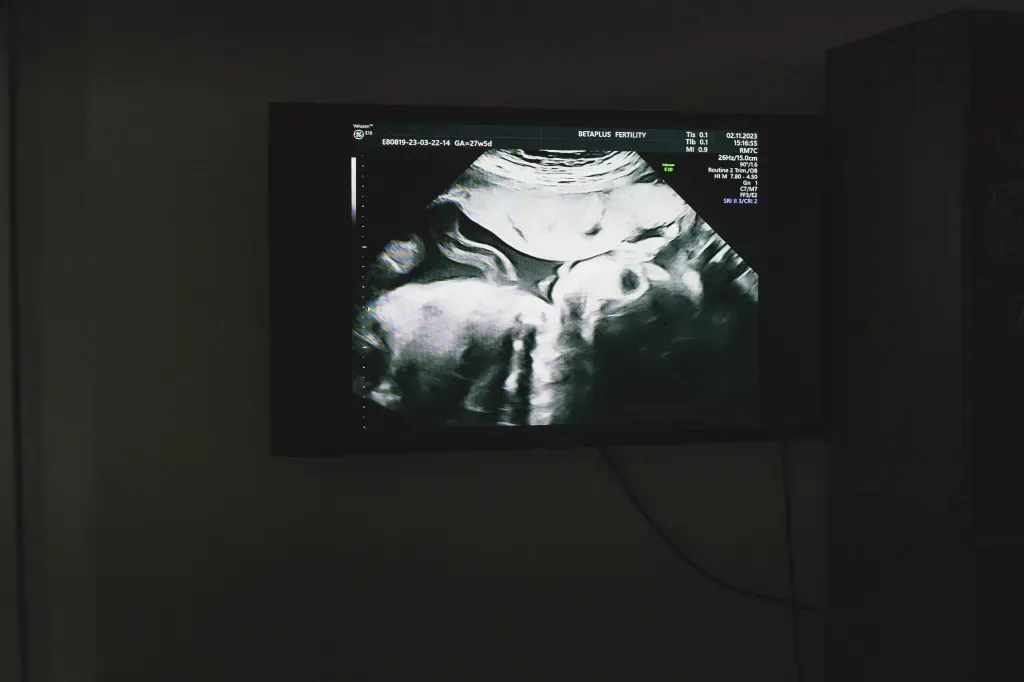

随后一系列复杂的流程全都由康德利搞定——匹配代理孕母(“代妈”),去公证处签订“准父母”(也就是王大哥和他的“女伴”)、捐卵者(“卵妹”)和“代妈”的三方代孕协议。“卵妹”在与康德利合作的辅助生殖诊所中促排、取卵,随后诊所实验室用王大哥的精子和“卵妹”的卵子进行人工授精,形成的胚胎在经过养囊、基因筛查等步骤后,被移植入孕母体内。再过几周,就能通过B超检查确定胚胎是否在孕母体内成功着床、是否出现胎心音,一旦有胎心,就意味着妊娠成功,开始进入怀孕管理阶段。